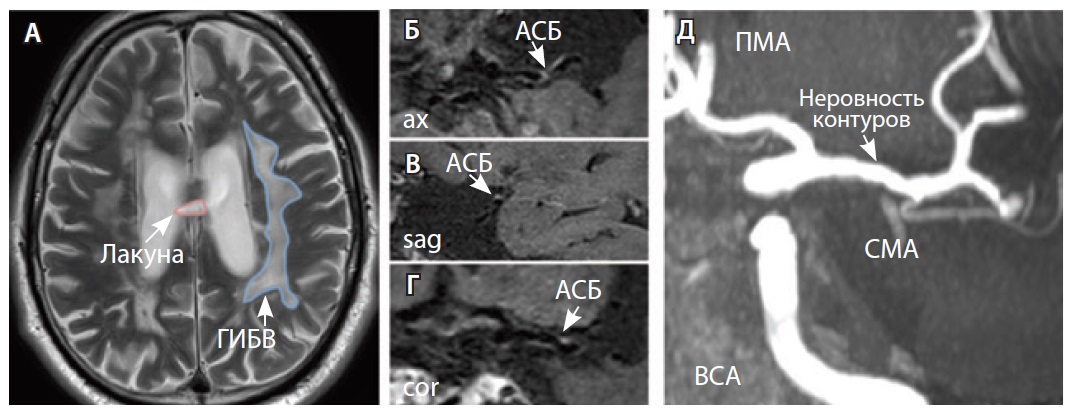

Рис. 4. Пациент К., 69 лет, с признаками церебральной микроангиопатии (F2 по шкале Fazekas) и атеросклерозом интракраниальных артерий, с формированием гемодинамически значимого стеноза в сегменте М1 правой средней мозговой артерии (СМА): А – магнитно-резонансная томография (МРТ), режим Т2-взвешенного изображения: видны множественные сливные очаги гиперинтенсивности белого вещества (ГИБВ); Б, В – МРТ сосудистой стенки, режим T1-TSE-db-FS после контрастного усиления: в сегменте М1 правой СМА визуализируется эксцентричная атеросклеротическая бляшка (АСБ), интенсивно накапливающая контрастный препарат; Г – трехмерная магнитно-резонансная времяпролетная (3D ToF) ангиография: виден стеноз правой СМА в сегменте М1; Д – режим HR Т2-TSE: видна АСБ в сегменте М1 правой СМА; ax – аксиальная, sag – сагиттальная плоскости; ЗМА – задняя мозговая артерия; ПМА – передняя мозговая артерия